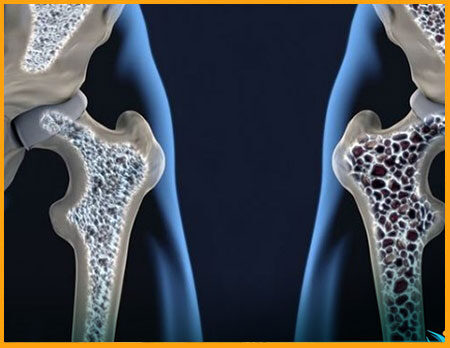

پوکی استخوان چیست؟ پوکی استخوان بیماری قرن نامیده میشود و جالب است بدانید که این بیماری بدون علامت است. فرد دارای پوکی استخوان عموما بدنبال کوچکترین تروما ویا سقوط دچار شکستگی در یکی از نواحی حساس میشود در این بیماری استخوانها دارای خلل و فرج بیش از حد شدهاند. این بیماری نوعی بیماری پیشرونده استخوان است که در آن جرم و دانسیته استخوان کم شده منجر به سست و شکننده شدن استخوان میشود. این بیماری در تمامی گروههای سنی و در هر [...]